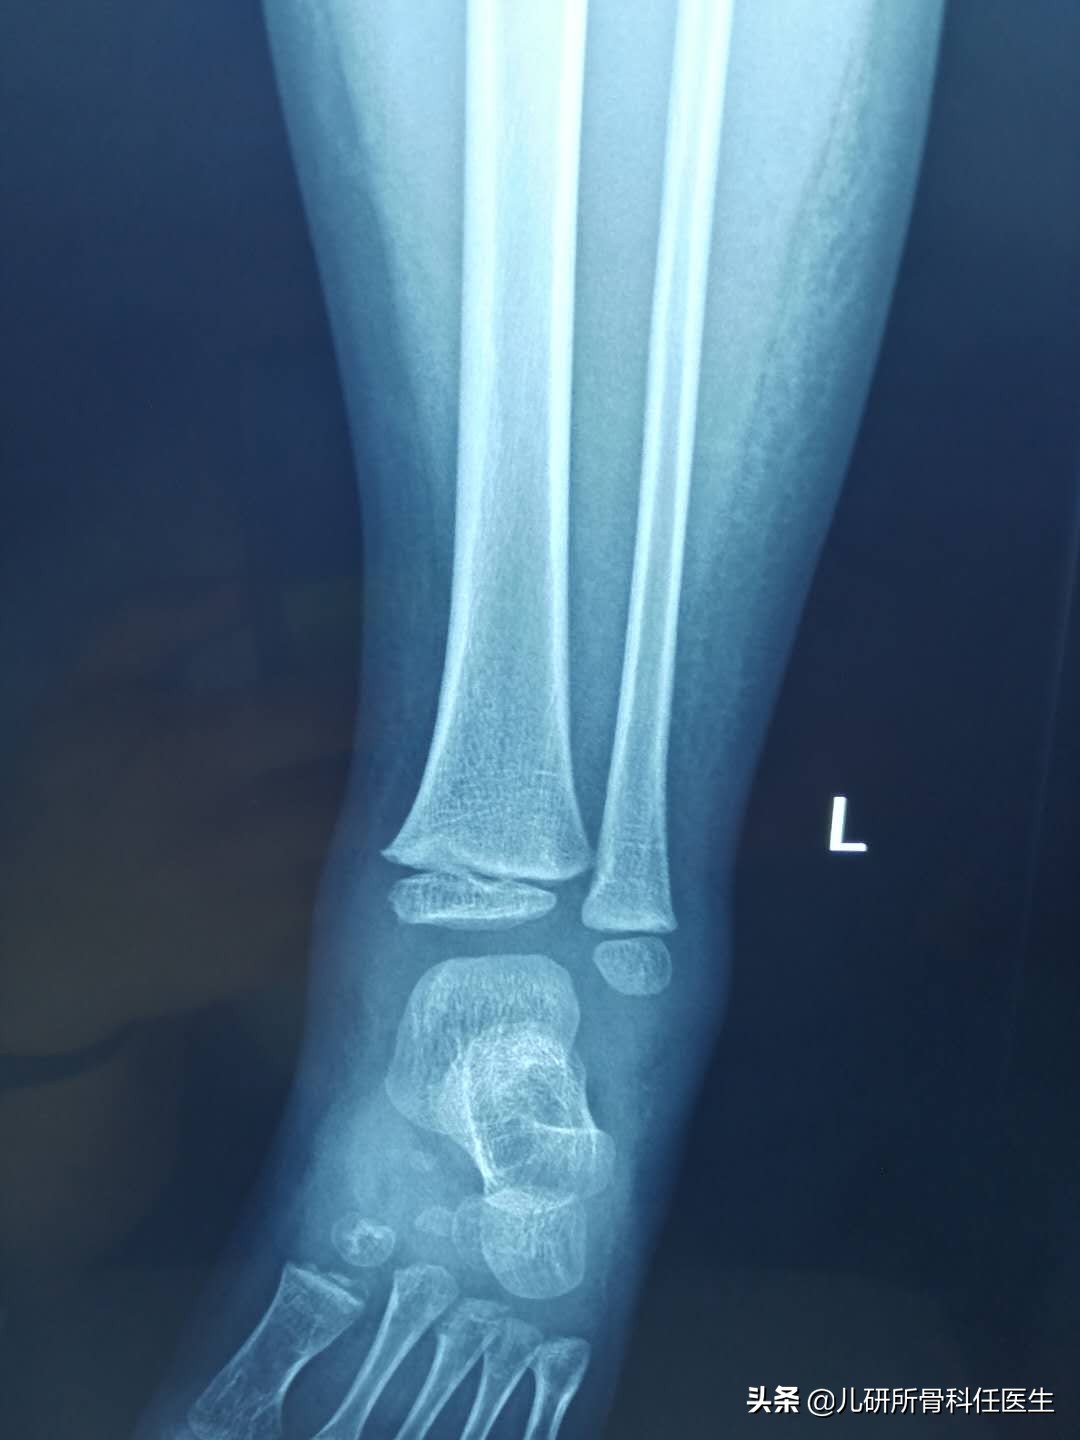

这种情况,根据我的经验,蚊虫叮咬的可能性很大,但是问孩子妈妈说没记得有蚊虫咬过(估计蚊子饱餐一顿后没有跟妈妈那里买单)。为了防止误诊和漏诊,任医生还是给孩子做了两项检查,一是拍了踝关节的正侧位x线片,同时查了血常规和C反应蛋白(儿研所的这两项检查只需要查指尖血就可以),主要是要排除骨损伤和软组织感染两种情况。

经过漫长的等待,结果出来了,X线提示未见明显骨损伤。